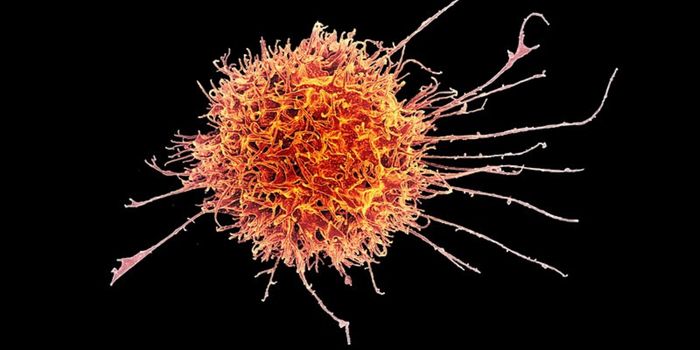

OCT 05, 2021ImmunologyMany of the deadly viruses that affect humans—including Ebola and HIV—have animal origins. These infectious ...